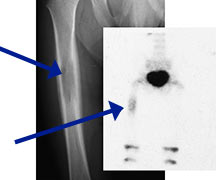

- May arise from any bone and any site within a bone (epiphyseal, metaphyseal, diaphyseal)

- Radiographically variable appearance: may appear benign (geographic) or malignant (permeative or moth eaten)

- Femur